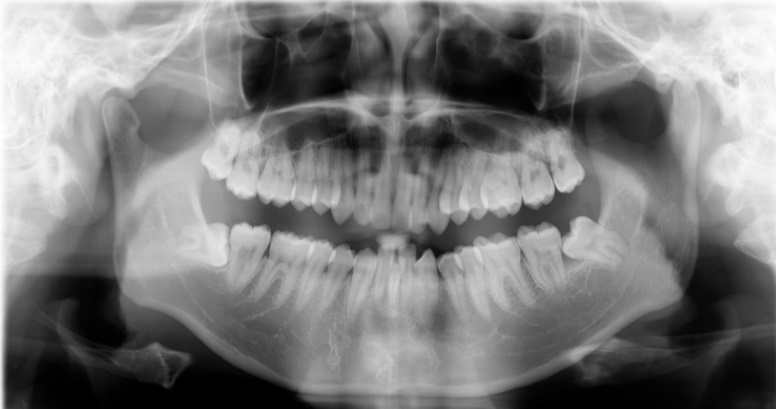

Bước 1: Khám lâm sàng và chụp Xquang

Bác sĩ sẽ khám lâm sàng chụp phim Xquang và kiểm tra tình trạng răng khôn của bạn có sâu vỡ không, có mọc lệch không, có gây ảnh hưởng đến răng bên cạnh không, từ đó sẽ tư vấn nhổ răng phù hợp.